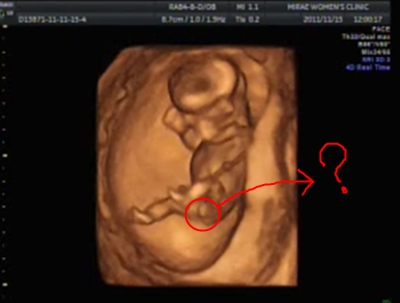

12ÁÖ 5ÀÏ ÃÎÆÄ±¸¿ä~ ±Ã±ÝÇØÇÏ´Â ¾ö¸¶¸¦ À§ÇØ ´Ù¸®µµ ¹ú·ÁÁÖ¾ú´Âµ~

¾ÆÁ÷ ¼ºº°Àº ¾È ¾Ë·ÁÁֽôõ¶ó±¸¿ä¤Ì¤Ì

´Ù¸¥ ¸¾µéÀº 12ÁÖ¶§ ¾Æ½Ã´Â ºÐµµ ¸¹À¸½Ã´øµ¥¿ä ºÎ·´ºÎ·´~!